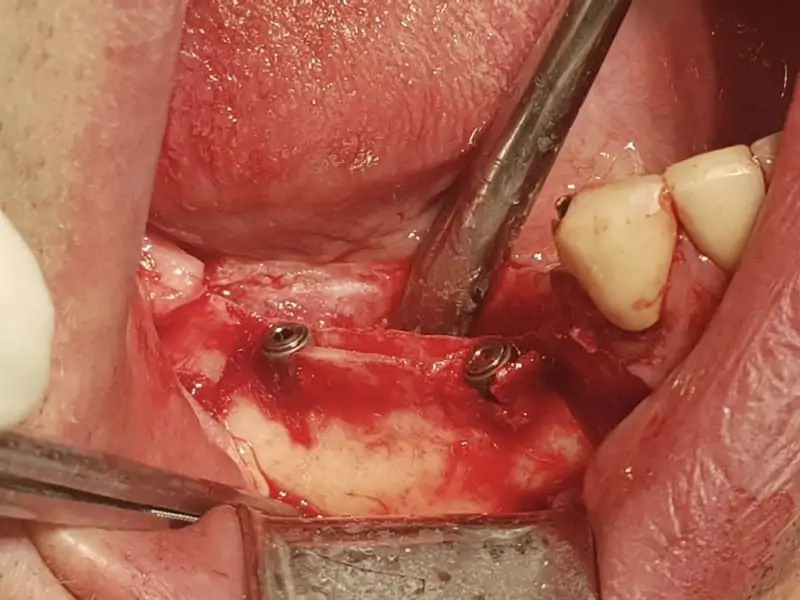

This is the case presenting crest split with immediate insertion of two 3P implants by BB dental along with bone augmentation with artificial bone Novocor plus, platelet rich fibrin, and resorbable membrane by BB Dental. The crest of lower jaw was less then 2mm wide and it was neccessary to split the bone using piezo surgery, mallet and chisel. In this way we were able to gain enough of bone width to place two implants both 3.5/10.

After the insertion of implants with good primary stability, we used PRF in combination with artificial bone Novocor plus to create “sticky bone” which is essential for new bone growth. This augmented implant site was covered with PRF membranes and then with BB dental collagene membrane. Prior to augmentation bone was drilled with roung burr in other to get blood vascularization. The flap was sutured with monofilament suture which is essential in proper wound healing.